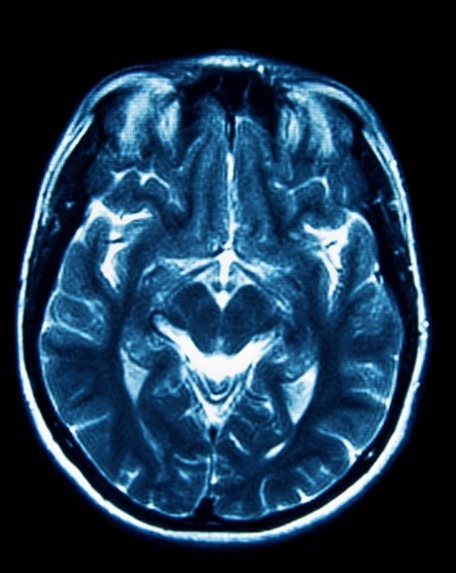

Detects brain tumors, liver disease, heart conditions, and bone fractures using X-rays and MRI scans.

Pre-trained ML and deep learning models for disease detection using medical imaging (CNNs for X-rays and MRIs, classifiers for structured data).